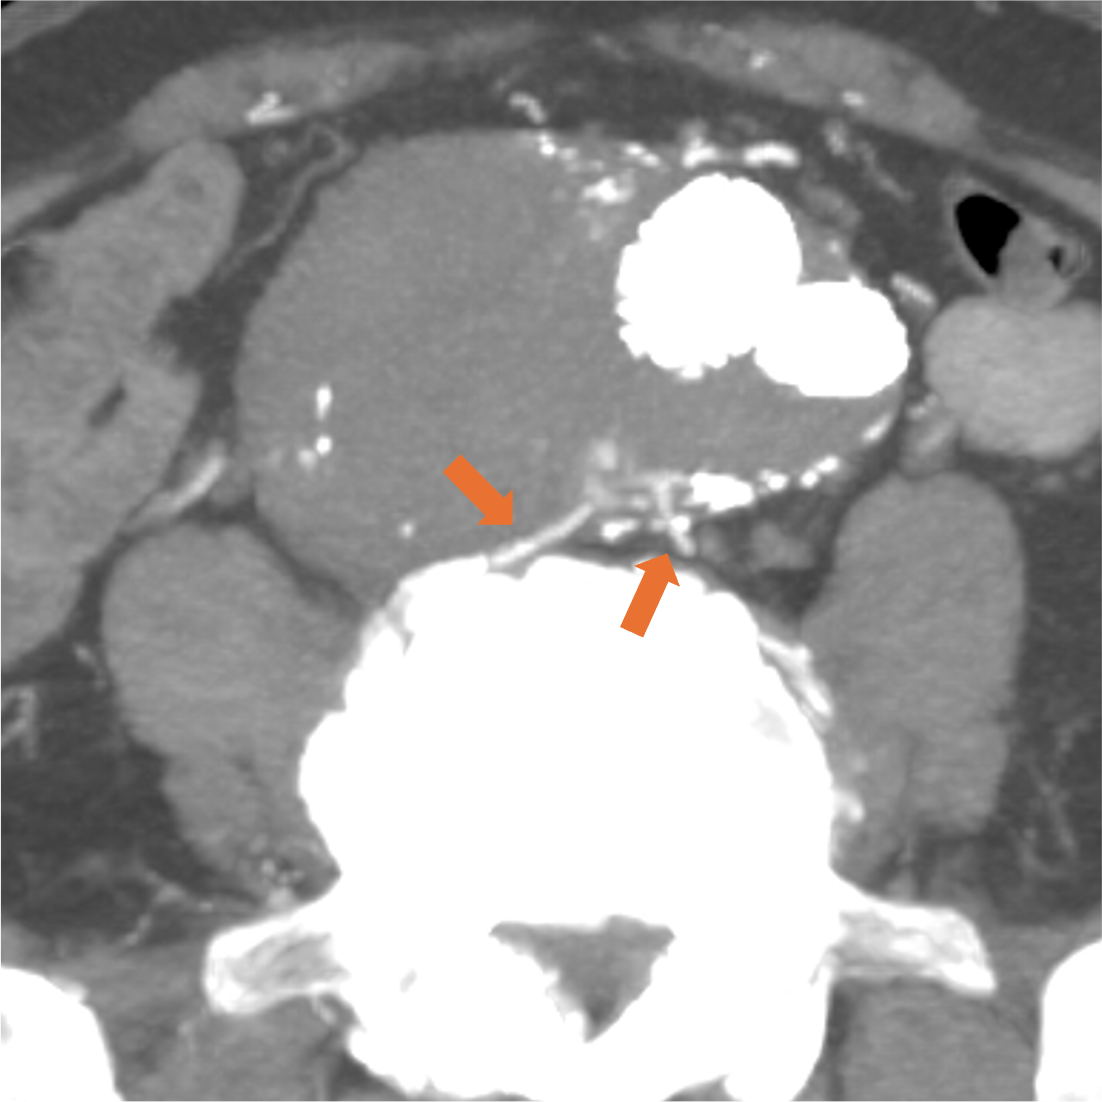

症例は80代男性。7年前に腹部大動脈瘤と右総腸骨動脈瘤に対しEVAR、2年前に腹部大動脈瘤のエンドリークに対し、下腸間膜動脈からコイル塞栓を行っている。動脈瘤が拡大傾向であったため、超音波検査が行われ、エンドリークが疑われた。評価と治療方針決定が必要と判断されたが、腎機能障害があったため入院での造影CTが計画された。

当該疾患の診断における造影CTの役割

CT技術や撮像プロトコル設定について

当院で使用されているCTは256列でのDual energy CTの撮影が可能なGEヘルスケア社のRevolution CTである。従来のSingle energy CTは1種類の管電圧を使用し、1種類のX線エネルギーを使用した撮像を行うが、本機種では高管電圧と低管電圧の2種類の異なる管電圧からそれぞれのX線エネルギーを使用した撮像が可能である。それにより、高画質かつ高コントラストの水密度画像とヨード密度画像が作成可能で、Deep learningを用いて解析を行うことでノイズの低減されたCT画像を再構成できる。本症例のようにTypeⅡエンドリークでは微小な血管が関与している場合があり、その検出と詳細な血管走行の確認において高コントラストかつ高画質の画像が求められ、Dual energy CTは有用である。